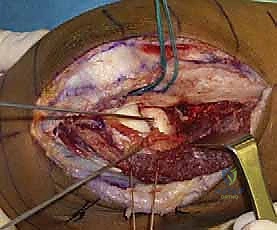

خطوات العملية الجراحية مع الأستاذ الدكتور محمد هطيف

إجراء جراحة في المرفق ليس بالأمر السهل، فهو يمر بأعصاب وأوعية دموية حساسة للغاية. إليك كيف تتم العملية بخطوات احترافية:

- التخدير والتحضير: يتم تخدير المريض (تخدير كلي أو موضعي للذراع) في بيئة جراحية معقمة بالكامل.

- الشق الجراحي الدقيق (Surgical Approach): يستخدم الدكتور هطيف شق "كوخر" (Kocher approach) أو "كابلان" (Kaplan approach) للوصول إلى مفصل المرفق بأقل ضرر ممكن للأنسجة العضلية المحيطة.

- حماية الأعصاب (Nerve Protection): يتم تحديد وحماية "العصب بين العظمين الخلفي" (PIN) بدقة متناهية باستخدام تقنيات الجراحة الميكروسكوبية لتجنب أي شلل أو ضعف في حركة الأصابع بعد العملية.

- التعامل مع الكسر: باستخدام مناظير المفاصل 4K أو الرؤية المباشرة، يتم تنظيف المفصل من الشظايا العظمية والدم المتخثر.

- التثبيت أو الاستبدال: يتم تثبيت العظم بالشرائح التيتانيوم الدقيقة، أو تركيب المفصل الصناعي بدقة هندسية تضمن تطابق مقاس المفصل الصناعي مع العظم الأصلي للمريض.

- إصلاح الأربطة والإغلاق: يتم خياطة الأربطة الجانبية الممزقة، ثم إغلاق الجرح بخياطة تجميلية لا تترك أثراً مشوهاً.